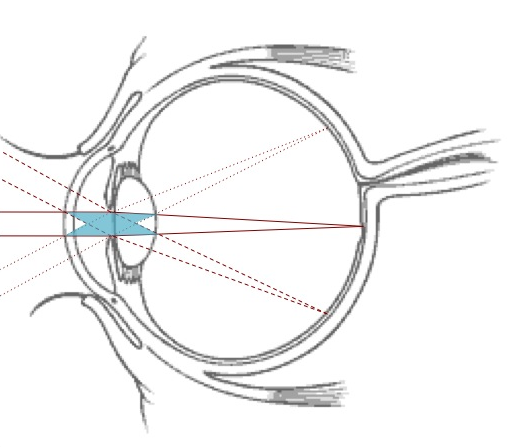

Let’s look at the cause of the field-of-view limitations in AO: wavefronts that are focused on different parts of the retina, cross different parts of the eye and thus incur different distortions. An AO correction that is valid along one direction is not valid along another direction. Assume that wavefront distortions are exclusively introduced at the entrance of the optical lens – this is the eye’s pupil, where wavefronts from all directions overlap. The distortions would then be the same whatever the field-direction. In this case the AO correction would be valid within large fields-of-view. In actuality, however, the distortions are introduced in at least 4 different planes: the front and back of the cornea and the front and back of the lens. Additional distortions are introduced by an index gradient within the optical lens. The temporal variations in these aberrations are caused by tear-film motions, blood pulsation and eye-movements. In multi-conjugate adaptive optics, deformable mirrors are optically conjugated to the planes where distortions are introduced. Each mirror corrects the distortions of its conjugate plane.